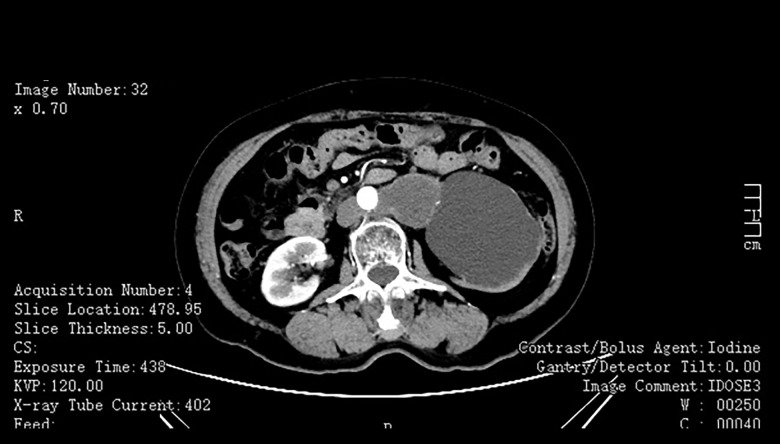

BACKGROUND Primary retroperitoneal tumors (PRTs) are uncommon, with retroperitoneal dermoid cysts being particularly rare. The cystic cavity of mature cystic teratomas (dermoid cysts) is lined with squamous epithelium and primarily filled with sebaceous material. These lesions often lack specific symptoms, leading to delayed diagnosis. Imaging modalities such as computed tomography (CT) and magnetic resonance imaging (MRI) are crucial for identifying these lesions, but definitive diagnosis relies on pathological examination. Surgical resection is the primary treatment, particularly for symptomatic or enlarging lesions. This report describes a case of a 78-year-old woman presenting with hydronephrosis secondary to a solitary retroperitoneal mature cystic teratoma (dermoid cyst) removed by laparoscopic resection. CASE REPORT A 78-year-old woman presented with left renal occupancy and severe hydronephrosis detected during routine health screening. Imaging studies revealed a retroperitoneal cystic mass compressing the upper urinary tract. She underwent laparoscopic resection of the mass and nephrectomy. Histopathological examination confirmed the diagnosis of an isolated retroperitoneal mature cystic teratoma. Postoperatively, she recovered well and remained asymptomatic during follow-up. CONCLUSIONS Retroperitoneal dermoid cysts are rare and pose diagnostic challenges due to their nonspecific clinical and imaging features. Early diagnosis and surgical intervention are critical to preventing complications and preserving organ function. This case report discusses the importance of preoperative evaluation and early treatment, highlighting the urgency of optimizing and standardizing the diagnosis and management of such diseases.

背景:原发性腹膜后肿瘤(prt)并不常见,尤其是腹膜后皮样囊肿。成熟囊性畸胎瘤(皮样囊肿)的囊腔衬有鳞状上皮,主要充满皮脂腺物质。这些病变通常缺乏特异性症状,导致诊断延迟。计算机断层扫描(CT)和磁共振成像(MRI)等成像方式对于识别这些病变至关重要,但最终诊断依赖于病理检查。手术切除是主要的治疗方法,特别是对于有症状的或扩大的病变。本报告报告一位78岁的女性,以腹腔镜切除单发腹膜后成熟囊性畸胎瘤(皮样囊肿)继发肾积水。病例报告一名78岁女性,在常规健康检查中发现左肾占位和严重肾积水。影像学检查显示腹膜后囊性肿块压迫上尿路。她接受了腹腔镜肿块切除术和肾切除术。组织病理学检查证实了一个孤立的腹膜后成熟囊性畸胎瘤的诊断。术后恢复良好,随访期间无症状。结论腹膜后皮样囊肿是罕见的,由于其非特异性的临床和影像学特征,给诊断带来了挑战。早期诊断和手术干预对预防并发症和保持器官功能至关重要。本病例报告讨论了术前评估和早期治疗的重要性,强调了优化和规范此类疾病的诊断和管理的紧迫性。